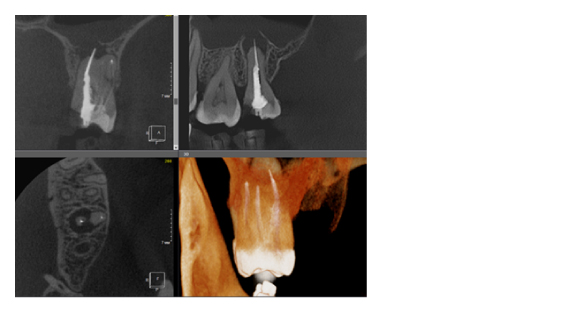

Рис. 1. Представлены два исследования (10x10 см и 20x20 см). На обоих изображениях хорошо видна канально-корневая система зубов, но, если масштабировать второе исследование, то качество неминуемо снизится, как и диагностическая эндодонтическая эффективность.

Рис. 3. КЛКТ с зоной сканирования 5x5 см и размером вокселя 70 микрон.